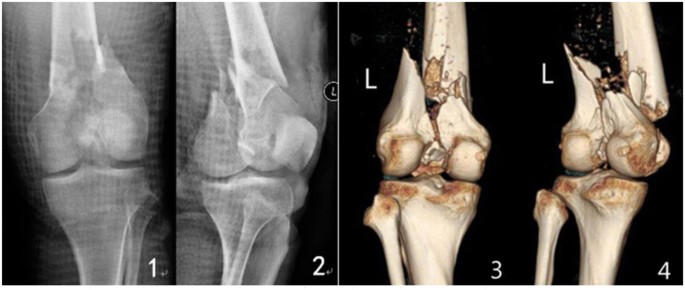

All patients were followed up for 12 to 48 months. The follow-up records of one patient of the double-plate group are shown in Figs 1–5 and those of one patient of the single plate group are shown in Figs 6 and 7. One patient in each group died one year and a half after the operation due to other causes. There were 58 patients and 60 cases of distal femoral fractures in total, of which one patient had bilateral distal femoral fractures both fixed by lateral plate and the other one with bilateral distal femoral fractures had a single plate on the right distal femur and double plates on the left. The age distribution of patients in the single-plate group and the double-plate group is shown in Table 1. There was no significant difference between the two groups (p = 0.330).

Inclusion criteria: Patients with distal femoral fractures treated with locking plate(s). Exclusion criteria: Patient with a decline of muscle strength of lower extremities. Anterior-Posterior and lateral plain film, computed tomography and 3D reconstruction of the fracture sites were performed to identify the fracture types.